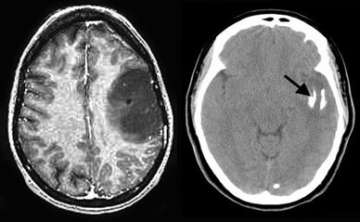

The MRI image (left) shows a large tumor in the left frontal lobe. The CT scan (right) shows that the tumor is partially calcified (arrow). The patient was successfully operated with awake speech mapping in the intra-operative MRI suite.

- Magnetic resonance imaging (MRI) is the preferred diagnostic tool, although computed tomography (CT) is important as well to document whether calcifications exist.